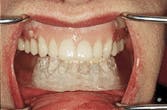

Figure 2-A diagnostic denture first is constructed if implants are planned or if the implants already have been placed. A diagnostic denture is constructed that satisfies the patient in the areas of esthetics, comfort and function.

Figure 2